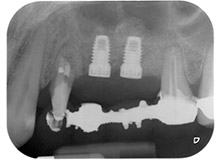

Фиг. 1: 58-годишна пациентка. Предоперативната рентгенография показва апикално-периодонтална лезия на зъб 24 и хоризонтална загуба на алвеоларна кост във втори квадрант.

58-годишна пациентка се оплаква от болка и повишена подвижност в нейния мост върху зъб 24 с функция на абатмънт. На лице е периодонтално възпаление с дълбочина на джоба 7 mm мезиобукално и повече от 12 mm дистално, както и включена 3 градусова фуркация. Освен това, рентгенографията показва обширна периодонтална лезия около апикалната зона на (друго място) предварително ендодонтски обработен зъб 24 (Фиг. 1).

В букалния корен, цялата вестибуларна и дистална кост липсва. Захващането е значително ограничено до палатиналния корен, подчертавайки предварително лошата прогноза. Зъб 27 също откри намалено хоризонтално захващане и минимално апикално разреждане (Фиг. 1) без клинични симптоми.

Фиг. 16: Следоперативната рентгенова снимка показва, че имплантите са на място и костозаместващия материал от вътрешния синус лифт около апекса. Има малко видим материал от GTR процедурата около каналите на зъб 24.